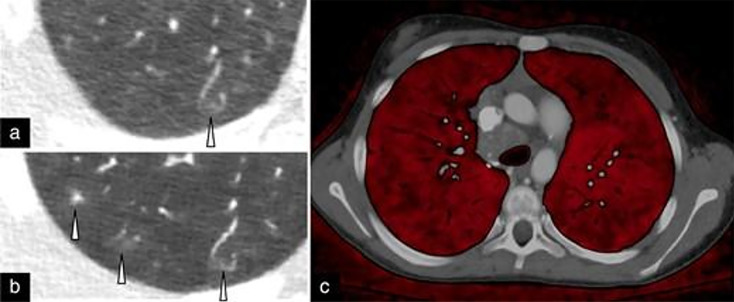

Photon-counting computed tomography (PCCT) represents a significant advancement in pediatric cardiovascular imaging. Traditional CT systems employ energy-integrating detectors that convert X-ray photons into visible light, whereas PCCT utilizes photon-counting detectors that directly transform X-ray photons into electric signals. This direct conversion allows photon-counting detectors to sort photons into discrete energy levels, thereby enhancing image quality through superior noise reduction, improved spatial and contrast resolution, and reduced artifacts. In pediatric applications, PCCT offers substantial benefits, including lower radiation doses, which may help reduce the risk of malignancy in pediatric patients, with perhaps greater potential to benefit those with repeated exposure from a young age. Enhanced spatial resolution facilitates better visualization of small structures, vital for diagnosing congenital heart defects. Additionally, PCCT's spectral capabilities improve tissue characterization and enable the creation of virtual monoenergetic images, which enhance soft-tissue contrast and potentially reduce contrast media doses. Initial clinical results indicate that PCCT provides superior image quality and diagnostic accuracy compared to conventional CT, particularly in challenging pediatric cardiovascular cases. As PCCT technology matures, further research and standardized protocols will be essential to fully integrate it into pediatric imaging practices, ensuring optimized diagnostic outcomes and patient safety.